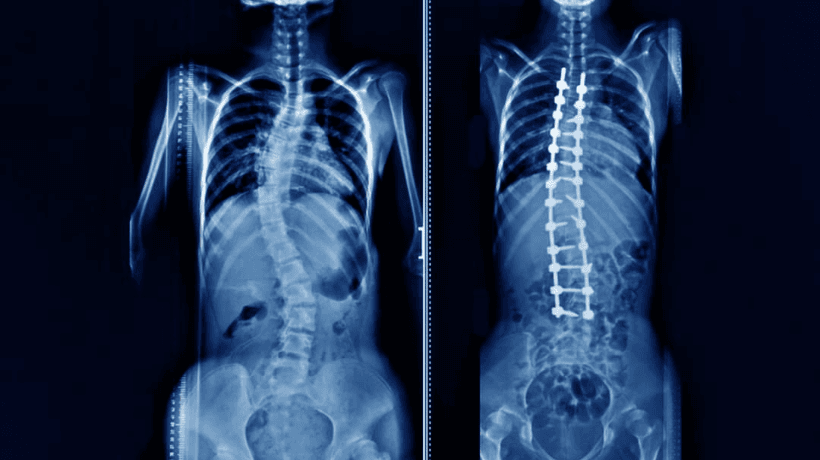

স্কোলিওসিসের অগ্রগতি এবং তীব্রতার উপর নির্ভর করে বিভিন্ন চিকিত্সার কৌশলগুলি সুপারিশ করা হয. হালকা থেকে মাঝারি স্কোলিওসিসের জন্য, বিশেষত এমন শিশুদের মধ্যে যাদের হাড় এখনও বাড়ছে, ব্র্যাকিং প্রায়শই মেরুদণ্ডের আরও বক্রতা রোধ করার পরামর্শ দেওয়া হয. ব্যবহৃত ধনুর্বন্ধনীগুলি লো-প্রোফাইল, প্লাস্টিক থেকে তৈরি এবং শরীরের সাথে মানানসই করার জন্য ডিজাইন করা হয়েছে, এগুলিকে কম অনুপ্রবেশকারী কিন্তু কার্যকর করে তোল. আরও গুরুতর ক্ষেত্রে, মেরুদণ্ডের ফিউশন বা মেরুদণ্ডের শরীরের টিথারিংয়ের মতো অস্ত্রোপচারের বিকল্পগুলি প্রয়োজন হতে পার. মেরুদণ্ডের ফিউশনটি চলাচল রোধ করতে দুটি বা ততোধিক মেরুদণ্ডের হাড় সংযোগ করা জড়িত, যখন ভার্টিব্রাল বডি টিথারিং বক্ররেখা সংশোধন করতে স্ক্রু এবং একটি নমনীয় কর্ড ব্যবহার কর.